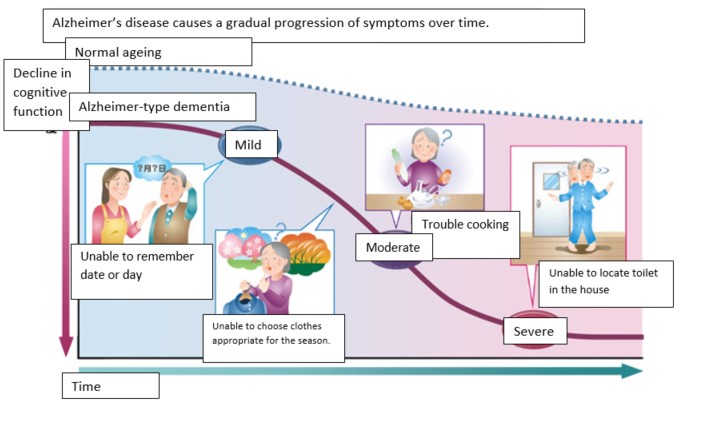

Stages of Alzheimer’s disease dementia

They are more likely to exhibit behavioural changes due to frustration and confusion in understanding their surroundings and conversations. The difficulties in expressing themselves may also cause misunderstandings with their caregivers. In the late or advanced stages of Alzheimer’s disease, one would become more confined to their own surroundings. Family and friends will have to exert more effort to communicate and understand the person living with dementia as they may lose the ability to verbalise or even perform their day-to-day activities.